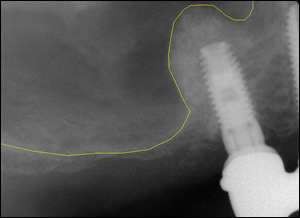

Fig4: The new position of the sinus and the integrated bone graft.